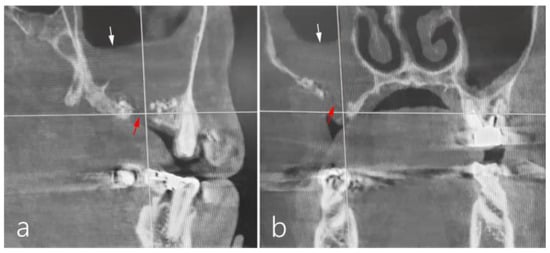

3. Discussion